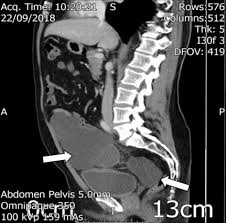

Figure 2 From Benign Multicystic Peritoneal Mesothelioma A Case Report Semantic Scholar

Figure 2 From Benign Multicystic Peritoneal Mesothelioma A Case Report Semantic Scholar from d3i71xaburhd42.cloudfront.net